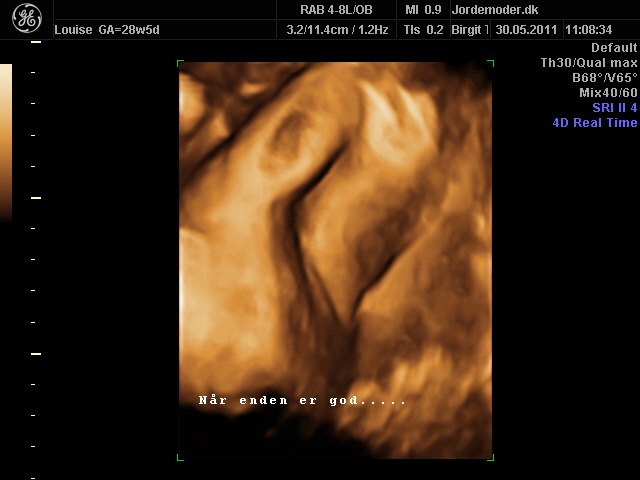

Så kom vi til 3d scanning igår. Lillepigen er slet ikke så stor som egen Jm kønnede hende HELDIGVIS! 1500 gram ca vejer hun nu, 28+6....

Hun har den fineste mund, jeg er helt misundelig på de smukker læber hun har.¨Ja hun er jo alt i alt bare dejlig, og jeg har ikke engang set hende sådan helt rigtig endnu.... Også har hun nogen gode runde kinder....

I skal ikke snydes for billeder af vores lille skønhed...